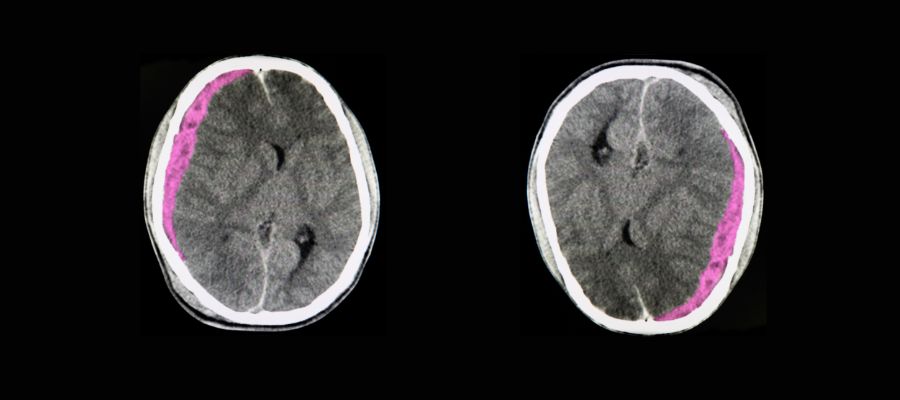

L'hématome sous-dural représente la complication la plus fréquente et la plus redoutable chez les seniors. Cette accumulation de sang entre le cerveau et la dure-mère peut se développer lentement, sur plusieurs jours ou semaines. Chez les personnes âgées, même un choc mineur peut provoquer cette lésion en raison de la fragilité accrue des vaisseaux sanguins et de l'atrophie cérébrale naturelle qui crée un espace plus important dans la boîte crânienne. Les symptômes peuvent inclure des maux de tête persistants, une somnolence progressive, des troubles de la mémoire ou des changements de comportement.